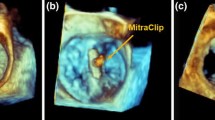

Mitral valve diseases are among the most prevalent heart diseases, and their prevalence increases with age.16 One of the most common defects of the mitral valve is mitral valve regurgitation (MR), affecting 7 million patients in the US annually.10 The traditional treatments for MR are surgical repair or replacement of the mitral valve (MV). However, as many as 49% of patients cannot undergo surgical treatment for severe degenerative MR due to advanced age, multiple comorbidities, and high surgical risks.23 There are several novel minimally-invasive therapies for mitral valve repair and replacement targeted to such patients.9 Pre-procedural planning of procedures such as transcatheter mitral valve repair (TMVR) is primarily based on digital anatomic models created from clinical imaging data. However, such digital-only modeling fails to incorporate the bidirectional deformation that occurs between the repair device and local mitral valve tissue as shown in Fig. 1. For example, when a nitinol TMVR (see Fig. 1a) device is deployed within a native mitral valve there are several deformation events that are expected: (i) the native mitral annulus is forced into a more circular configuration by the device; and the fully expanded device is compressed by the native annulus. This is an important aspect of device sizing since anchoring of the device often requires a 10–15% oversizing against the native annulus, thus creating consistent radial tension by the nitinol frame. (ii) The TMVR device necessarily displaces both anterior and posterior mitral leaflets into a vertical position within the LV (see Figs. 1b and 1c). The displaced anterior leaflet can create significant LVOT obstruction, however the magnitude of anterior leaflet displacement is constrained by its attachment to the chordae tendineae. As such, the sub-valvular apparatus may constrain the TMVR device deployment within the LVOT region or influence the final alignment of the entire device frame. Thus, there is need to develop patient-specific physical models to better inform patient and device selection protocols. The consideration of these deformation outcomes could influence the clinical decisions about type of TMVR device (e.g. self-expanding nitinol frame vs balloon-expandable cobalt-chromium frame); the size of the device for a specific patient; or even the decision to proceed with high risk surgery to avoid a predicted poor outcome with TMVR.

Bidirectional deformation of cardiac tissue and device. (a) Nitinol transcatheter mitral valve replacement (TMVR) device (Intrepid, Medtronic, USA); (b) Computed tomography image of the TMVR device implanted into a 3D printed mitral valve model incorporating tissue-specific material properties. (c) View from the left ventricle of the TMVR device deployed within a 3D printed mitral valve model. Regions of device and tissue deformation of the annulus (a), leaflet (l), and chordae tendineae (c) are identified (red ovals).